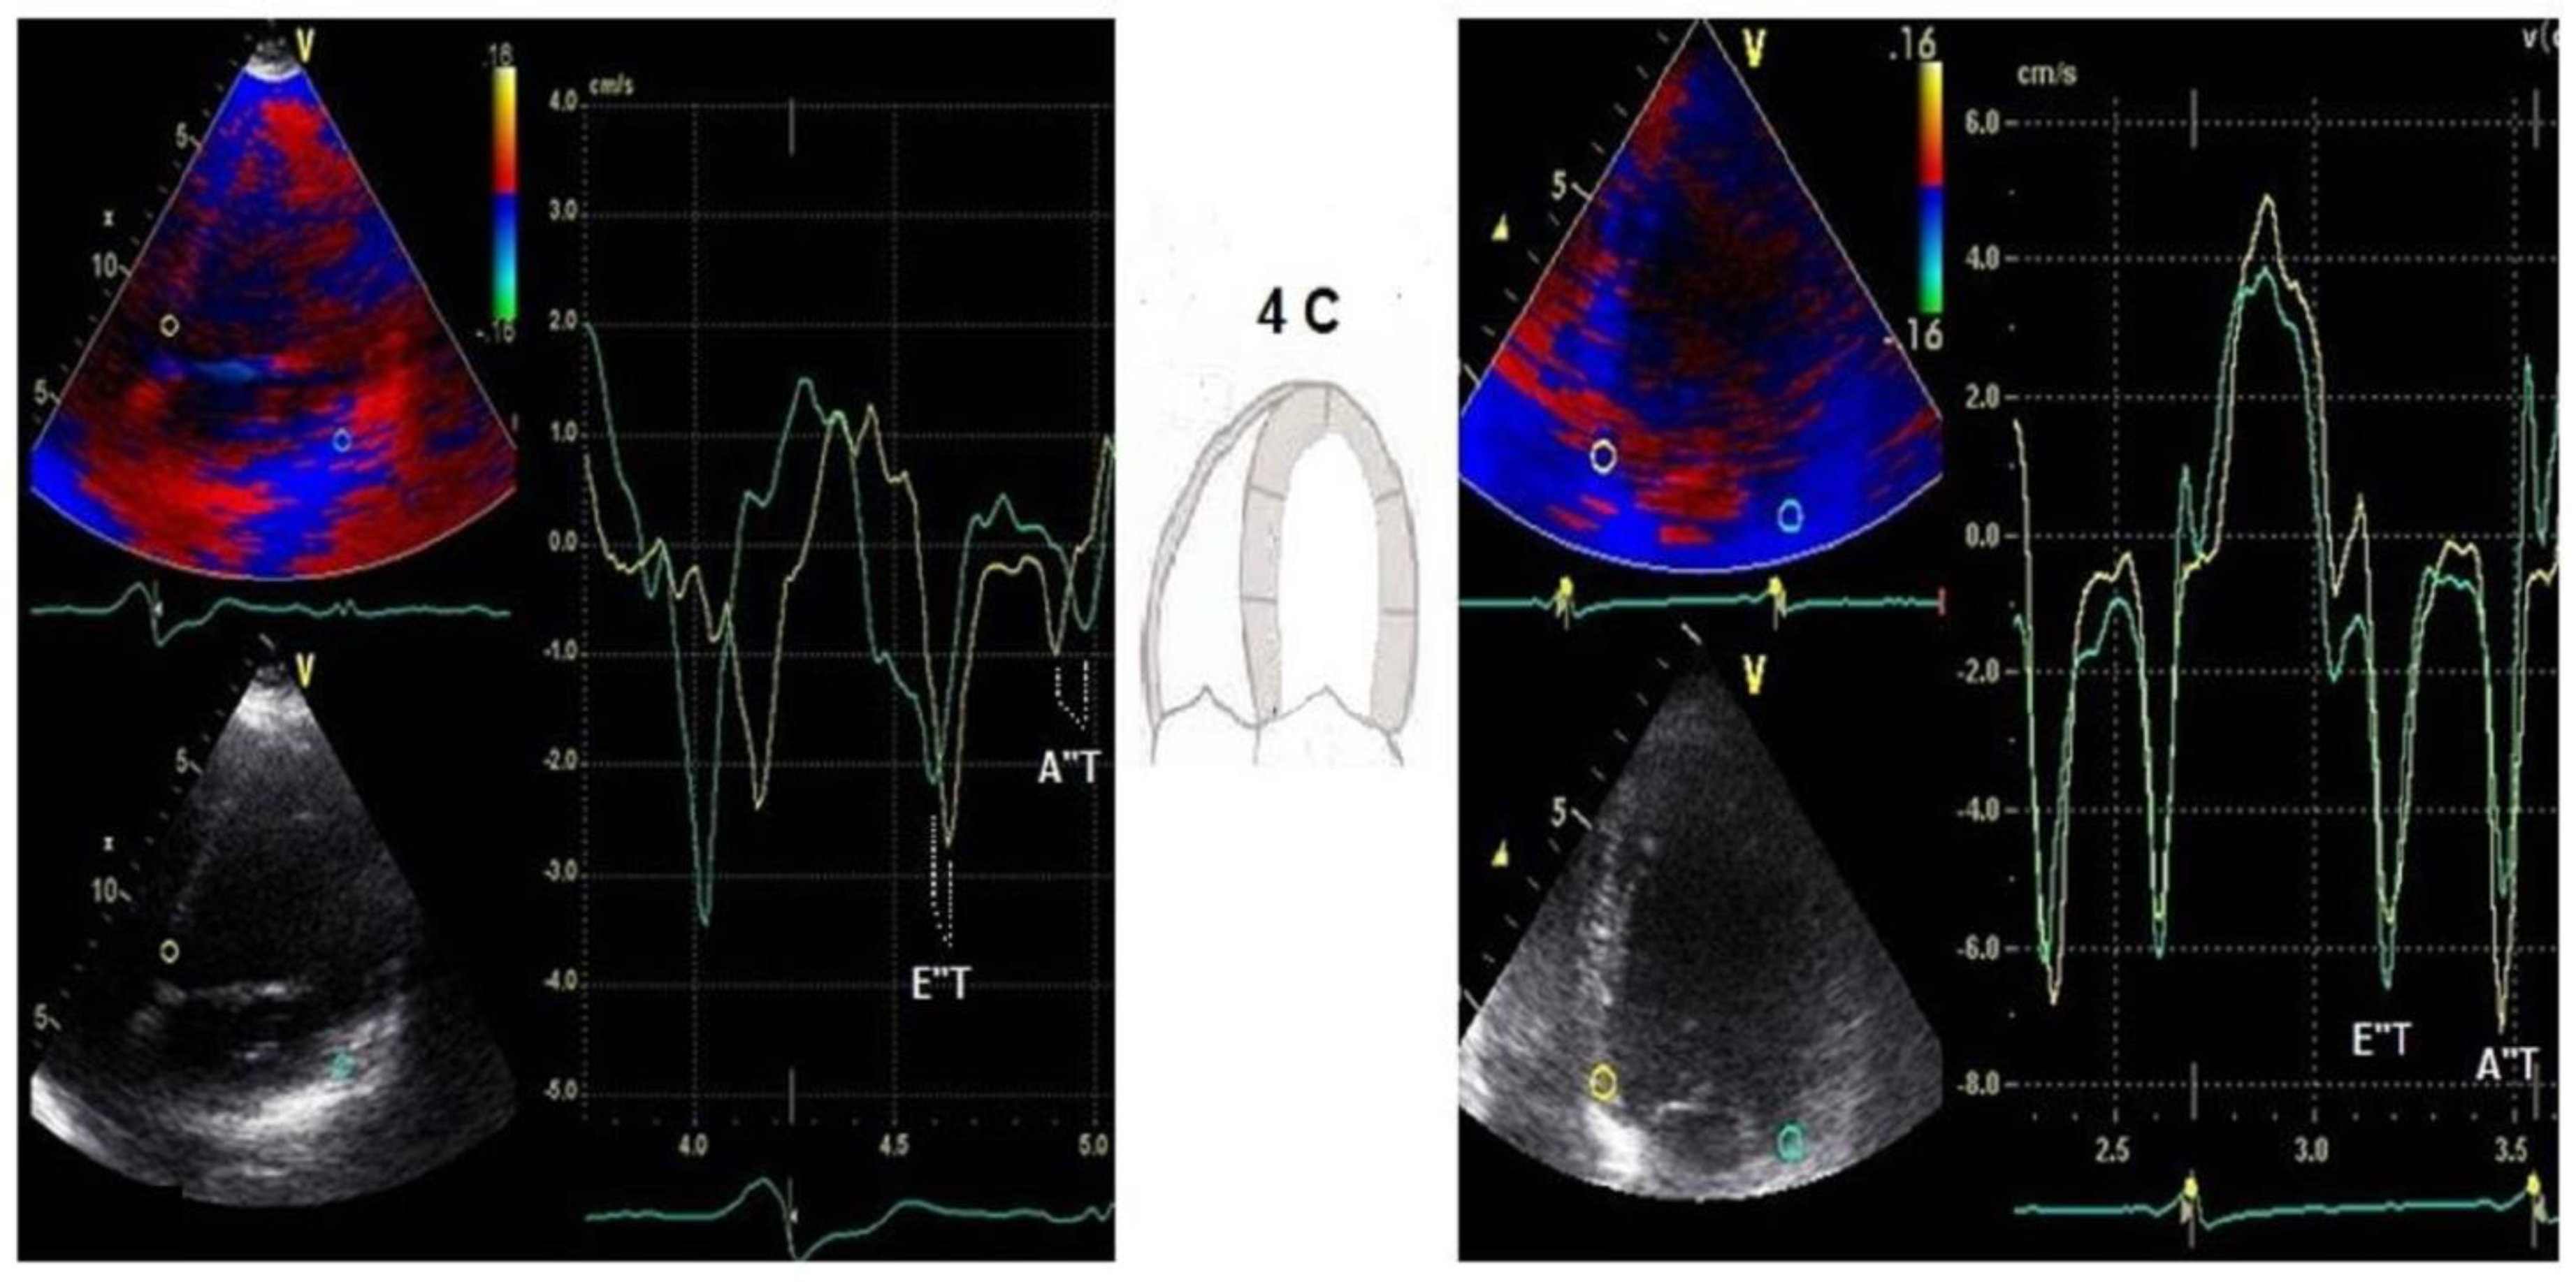

Evaluation of diastolic dyssynchrony was performed in the diastolic phase by offline speckle-tracking-derived TDI timing assessment of the simultaneity of E″ and A″ basal septal and lateral wall in a 4-chamber view. In addition, we defined the following new parameters: E″ and A″ time (E″T/A″T) as the time difference between the septal and lateral wall E″ and A″ peaks (Figure 1). We measured these two new parameters outside ejective phase before and after resynchronization therapy. We performed a quantitative measurement in the time domain, which after CRT decreased, improving the diastolic filling time and therefore the mechanical efficiency and cardiac output.

Figure 3.

Example of a patient with baseline prolonged E″T and A″T and after 6 months of CRT; green line = lateral velocity curve, yellow line = septal velocity curve.